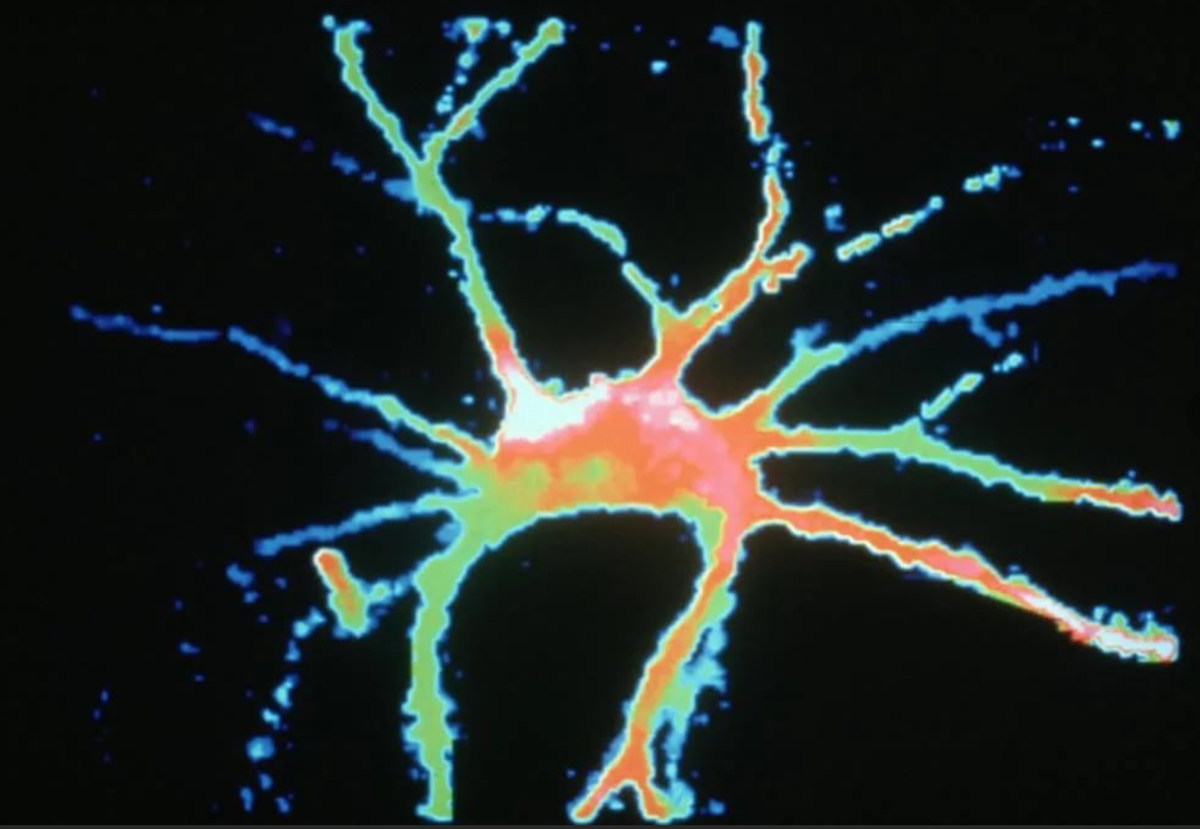

Моторный нейрон спинного мозга

Credit: Prof David Becker, Wellcome Images

Перед вами — конфокальное изображение моторного нейрона спинного мозга крысы. В клетки вводили флуоресцентный краситель, затем делали виртуальную «секцию» нейронов, а затем обратно собирали из нескольких фрагментов картинку, получая «тепловую высотную карту» нейрона, раскрашенную от синего к красному. Снимок вошёл в число финалистов премии Wellcome Image Awards в 1997 году.